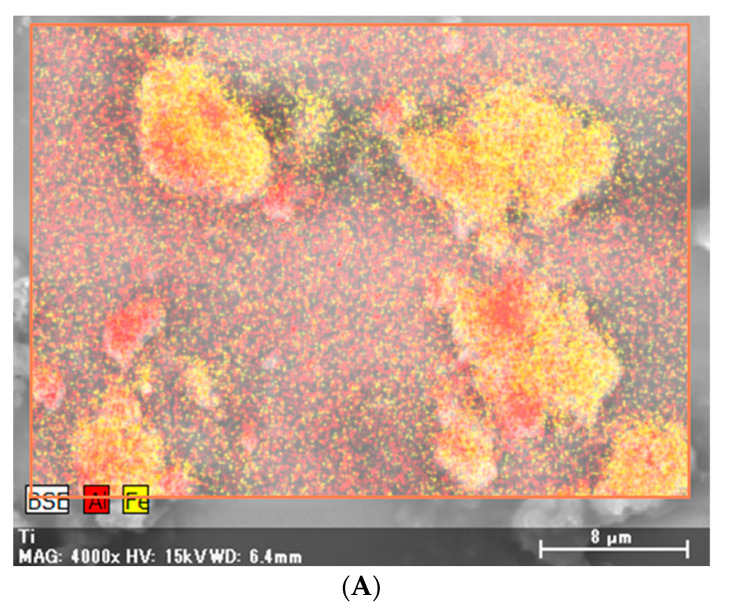

X-ray analytical electron microscopy (S-4500 Hitachi, Japan) of the same specimens detected particles containing aluminum, iron, titanium, and silica (Figure 4).

Non-necrotizing granulomas are observed in several lung diseases, including sarcoidosis, and their causes can be broadly classified into infectious and noninfectious factors. Noninfectious factors include the inhalation of organic and inorganic agents [ref. 14,ref. 15]. CBD is a well-known type of pneumoconiosis with a sarcoid-like reaction, which is caused by beryllium exposure, and shares several clinical and histopathological features with sarcoidosis [ref. 1,ref. 16,ref. 17]. Similar manifestations have occasionally been reported in cases of exposure to dust of other metals, such as aluminum, titanium, silica, and zirconium [ref. 2,ref. 3,ref. 4,ref. 5,ref. 6,ref. 7,ref. 8,ref. 9,ref. 10,ref. 11,ref. 12,ref. 13]. Our patient showed non-necrotizing granulomatous inflammation with chronic-multinucleated giant cells and marked dust deposition without a history of beryllium exposure; additionally, aluminum, iron, titanium, and silica were detected in the deposited dust in the lung specimens. Therefore, we suspected the development of pneumoconiosis with a sarcoid-like reaction in our patient due to exposure to occupational dust of metals other than beryllium.

In this case, X-ray analytical electron microscopy detected aluminum, iron, titanium, and silica deposition in the lung tissues. In four case reports of pneumoconiosis with a sarcoid-like reaction other than CBD, detailed mineralogical analyses were performed and the following were detected in the lung tissues: aluminum and silica due to limestone exposure; aluminum, silica, and magnesium due to glass wool fiber exposure; silica and iron due to toner dust exposure; and aluminum, magnesium, and silica due to metal reclamation factory exposure [ref. 4,ref. 8,ref. 9,ref. 10,ref. 13]. Additionally, aluminum, silica, and titanium were detected in the lung tissues of six patients with pneumoconiosis with a sarcoid-like reaction due to man-made mineral fiber exposure [ref. 2]. Other studies have also shown that aluminum and silica are frequently detected in patients with pneumoconiosis with a sarcoid-like reaction [ref. 3,ref. 7]. We cannot ignore the effects of silica, as it is detected in most lung samples of various lung diseases, regardless of the extent of occupational exposure [ref. 22,ref. 23].

Aluminum is frequently detected in patients with occupational exposure [ref. 22,ref. 23] and can cause pulmonary fibrosis, referred to as aluminosis or aluminum lung [ref. 24,ref. 25]. Pathological findings include interstitial fibrosis and, occasionally, granuloma [ref. 24,ref. 26]. Aluminum has also been listed as an inorganic agent in the etiology of sarcoidosis [ref. 14]. Collectively, we speculate that aluminum may play a particularly important role in the pathology of pneumoconiosis with a sarcoid-like reaction.